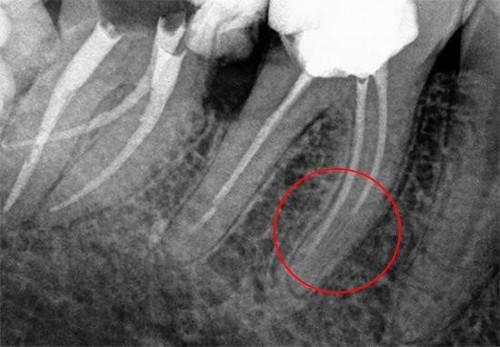

Почему болит зуб под коронкой? Причиной этому может быть и наличие инородного тела в канале. В ходе эндодонтического лечения может произойти отлом кончика инструмента, последующее пломбирование канала с инородным телом приводит к болям. Причин отлома может быть несколько - самой распространенной из них является кривизна каналов. Если они труднопроходимы, инструмент может сломаться в связи с высокой нагрузкой.

Как правило, в таком случае пациент чувствует боль при воздействии температур, а также болит зуб под коронкой при надавливании. Пульсация может появляться при нагрузке, жевании на стороне с установленной коронкой. Постукивание по зубу также вызывает неприятные ощущения.

Для того, чтобы избежать такого осложнения, врач-стоматолог обязательно выполняет рентген-диагностику перед установкой коронки или любого другого зубного протеза.